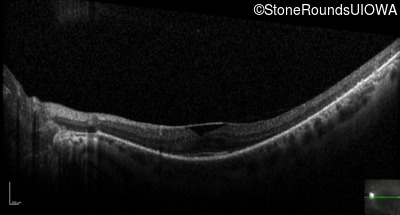

Optical Coherence Tomography - Right - 20/25 -2 sc

Exemplar / OCT Stack

OCT Stack